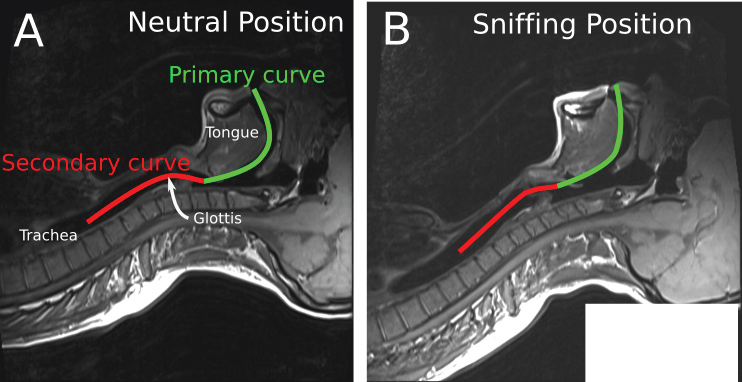

A review of the conditions for the initial laryngoscopy should be performed. The patient should be in the "sniffing" position with the neck flexed on the trunk and the head extended on the neck. This will align the oral, pharyngeal and laryngeal axes as much as possible (Figure 1). If the patient is obese, they should lie on a ramp to optimize the view at laryngoscopy.

Figure 1: Alignment of the oral, laryngeal and pharyngeal axes with the intubator's visual axis in the "Sniffing Position" as seen on an MRI scan [47]. Part of the figure was adopted from Greenland KB, et al. BJA. 2010;105(5):683-90. published by Elsevier with permission.